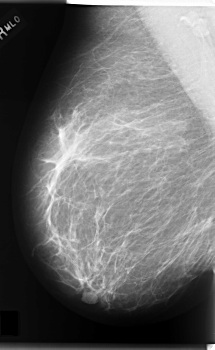

C_0164_1.LEFT_MLO

LEFT_MLO LINES 5888 PIXELS_PER_LINE 3816 BITS_PER_PIXEL 12 RESOLUTION 50 OVERLAY